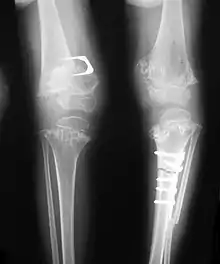

Accurate assessment of plain radiographic findings remains an important contributor to diagnosis of pseudoachondroplasia. It is noteworthy that vertebral radiographic abnormalities tend to resolve over time. Epiphyseal abnormalities tend to run a progressive course. Patients usually suffer early-onset arthritis of hips and knees. Many unique skeletal radiographic abnormalities of patients with pseudoachondroplasia have been reported in the literature.[2][7][4]

- Together with rhizomelic limb shortening, the presence of epiphyseal-metaphyseal changes of the long bones is a distinctive radiologic feature of pseudoachondroplasia.

- Dysplastic/hypoplastic epiphyses especially of shoulders and around the knees.

- Metaphyseal broadening, irregularity and metaphyseal line of ossification. These abnormalities that are typically encountered in proximal humerus and around the knees are collectively known as “rachitic-like changes”.

- Radiographic lesions of the appendicular skeleton are typically bilateral and symmetric.